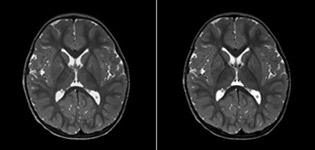

Pseudo-continuous arterial spin labeling (pCASL) was developed for brain perfusion imaging without contrast agent. “This is very desirable in pediatric patients where the general trend is to limit the administration of contrast,” says Dr. Miller. Growing confidence in specific applications “We built up confidence in pCASL by comparing it to contrast-based perfusion imaging. Once we had confidence that it was representing what the contrast perfusions were representing, we increased our diagnostic confidence by serial imaging in either the acute stage or the long term stages in a number of patients with arterial abnormalities.

Dr. Miller uses pCASL for all patients who present with chronic and acute cerebrovascular abnormalities such as acute stroke, as well as patients who present with signs of acute inflammation in the brain, and occasionally in patients with tumors, to assess the perfusion status of their tumor.

“In combination with diffusion weighted imaging, it can help give a more extended assessment of the degree of perfusion abnormality in a patient who is suffering acute ischemia. We have a number of patients who have chronic arterial insufficiency due to prior arterial abnormalities or acquired arterial abnormalities such as sickle cell disease or neurofibromatosis. Sometimes the child’s first manifestation of disease progression is a reduction in brain perfusion before stroke symptoms manifest clinically or in diffusion weighted imaging. We use pCASL to help delineate the perfusion abnormality.”

To other new users I would recommend to also start to interpret the pCASL images in comparison with other standard imaging – T2 and FLAIR and DWI – until the user gains confidence in interpreting these images by themselves.” “A powerful use of pCASL is in patients with chronic cerebrovascular stenosis, where clinicians desire information on how compensatory mechanisms of the brain are performing to enable perfusion to the brain. Often clinicians take into account how the compensatory mechanisms appear to help to provide adequate perfusion to the patient’s brain, and they may intervene surgically or make some other management decision.” “Another special application is the assessment of cerebrovascular reactivity with a Diamox perfusion exam, where we subtract two sets of pCASL images.”

“pCASL has now become more of a first-line scan for assessing perfusion for us, as opposed to DSC-based perfusion imaging with contrast agent. And in patients who were not planned to have contrast, we can perform pCASL for perfusion imaging without need to stop the exam, pull the patient out, and put in an IV. It also negates the postprocessing that’s necessary for dynamic susceptibility contrasts. And it allows us to repeat perfusion imaging in the same patient at the same imaging time, which is helpful in terms of patient motion, or in a situation where a scan needs to be done before pharmacological perfusion imaging.”